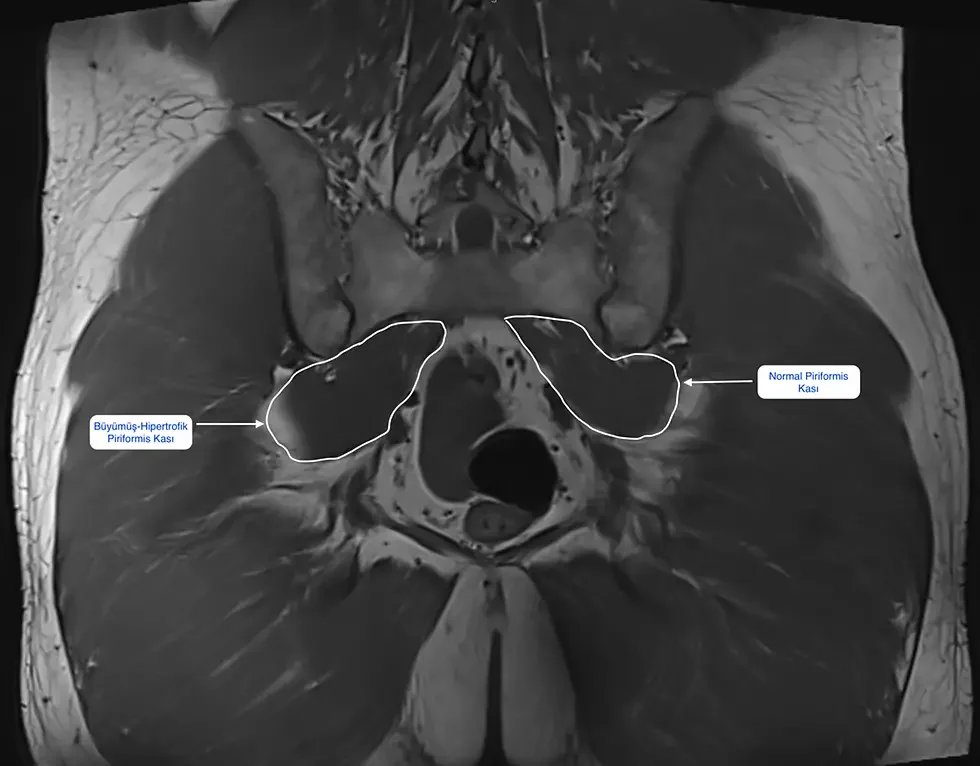

- Pelvis veya kalça MR’ında piriformis kasında kalınlaşma veya ödem aranabiliyor (her zaman görülmeyebilir),

- MR veya ultrason incelemesinde piriformis kasında ciddi kalınlaşma, ödem veya çevre dokularla yapışıklık izlenmesi,